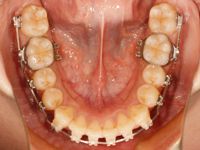

まずは調整前のお口の中です![]()

カレーを食べたせいか、ゴムが黄色く変色してますね![]()

そして、今回の調整後のお口の中です![]()

上顎のワイヤーは前回と同じです![]()

想像していたより上顎の歯並びに変化が無かったので、今回は上の歯を後ろ方向へ引っ張る力を強くしました![]()

下顎の方は一番硬いワイヤーに変えました

これで上の前歯が出ている感じが無くなってくるのを祈ります![]()